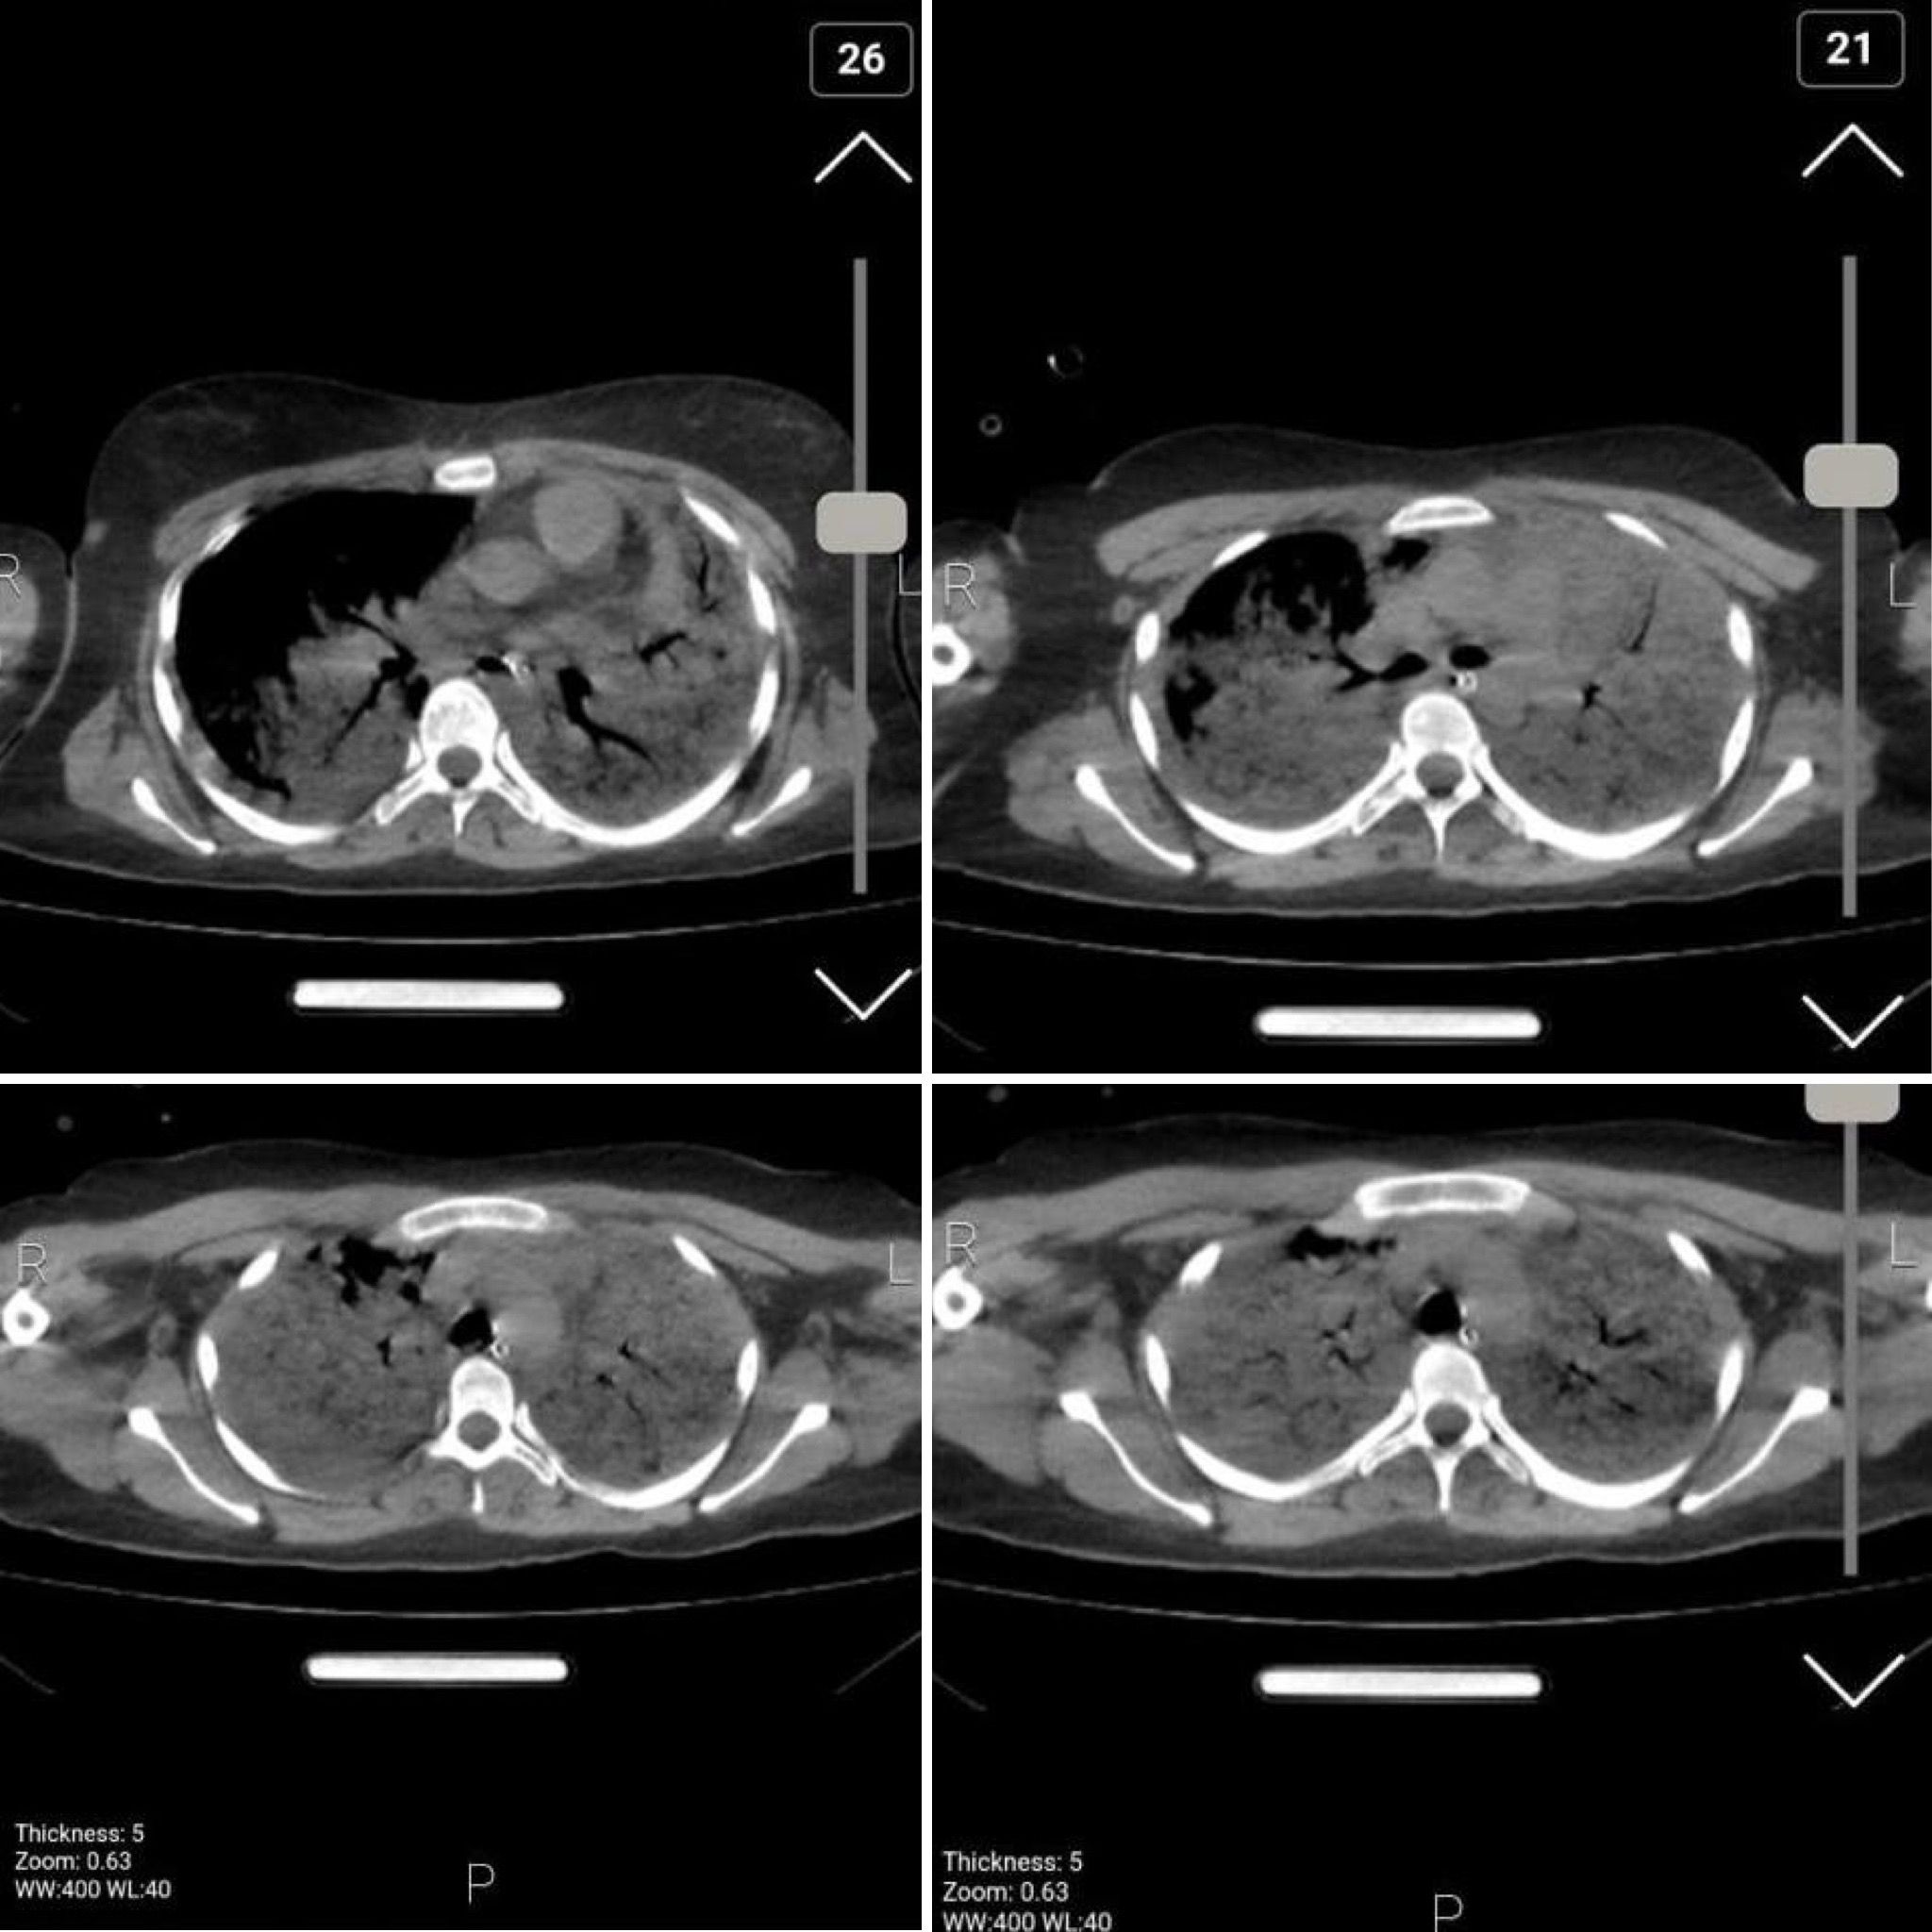

Images of her chest show bilateral diffuse alveolar hemorrhage and damage due to aspiration pneumonia, secretion retention and superimposed infection. Doctors say the results are compatible with acute respiratory distress syndrome due to brain trauma.